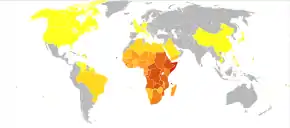

Schistosomiasis affected about 236.6 million people worldwide in 2019.[12] An estimated 4,400 to 200,000 people die from it each year.[7][8] The disease is most commonly found in Africa, Asia, and South America.[5] Around 700 million people, in more than 70 countries, live in areas where the disease is common.[7][13] In tropical countries, schistosomiasis is second only to malaria among parasitic diseases with the greatest economic impact.[14] Schistosomiasis is listed as a neglected tropical disease.[15]

Epidemiology

The disease is found in tropical countries in Africa, the Caribbean, eastern South America, Southeast Asia, and the Middle East. S. mansoni is found in parts of South America and the Caribbean, Africa, and the Middle East; S. haematobium in Africa and the Middle East; and S. japonicum in the Far East. S. mekongi and S. intercalatum are found locally in Southeast Asia and central West Africa, respectively.

The disease is endemic in about 75 developing countries and mainly affects people living in rural agricultural and peri-urban areas.[71][72][41]

| Intestinal | Schistosoma mansoni | Africa, Middle East, Caribbean, Brazil, Venezuela, Suriname |

| Intestinal | Schistosoma japonicum | China, Indonesia, Philippines |

| Intestinal | Schistosoma mekongi | Cambodia, Laos |

| Intestinal | Schistosoma guineensis | Central Africa rain forest |

| Intestinal | Schistosoma intercalatum | Central Africa rain forest |

| Urogenital | Schistosoma haematobium | Africa, Middle East, Corsica |

Infection estimates

In 2010, approximately 238 million people were infected with schistosomiasis, 85 percent of whom live in Africa.[73] An earlier estimate from 2006 had put the figure at 200 million people infected.[74] As of the latest WHO record, 236.6 million people were infected in 2019.[12] In many of the affected areas, schistosomiasis infects a large proportion of children under 14 years of age. An estimated 600 to 700 million people worldwide are at risk from the disease because they live in countries where the organism is common.[7][72] In 2012, 249 million people were in need of treatment to prevent the disease.[75] This likely makes it the most common parasitic infection with malaria second and causing about 207 million cases in 2013.[72][76]

S. haematobium, the infectious agent responsible for urogenital schistosomiasis, infects over 112 million people annually in Sub-Saharan Africa alone.[77] It is responsible for 32 million cases of dysuria, 10 million cases of hydronephrosis, and 150,000 deaths from kidney failure annually, making S. haematobium the world's deadliest schistosome.[77]